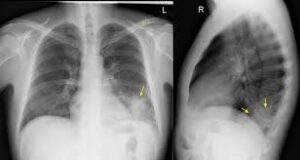

Pleural effusion sometimes referred to as “water on the lungs,” is the build-up of excess fluid between the layers of the pleura outside the lungs. फुफ्फुसीय आवरण रिसाव को कभी-कभी “फेफड़ों पर पानी” के रूप में संदर्भित किया जाता है, फेफड़ों के बाहर फुफ्फुस की परतों के बीच अतिरिक्त तरल पदार्थ का निर्माण होता है। The pleura are thin membranes that line the lungs and inside of the chest cavity and act to lubricate and facilitate breathing. फुस्फुसावरण पतली झिल्ली होती है जो फेफड़ों और छाती गुहा के अंदर की रेखा बनाती है और श्वास को चिकना और सुगम बनाने का कार्य करती है।